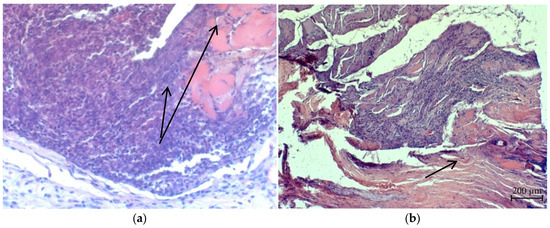

3.4. Investigation of Ag NPs and the Oxidized Ag NPs as a Covering Component of Suture Materials

- Rzhepakovsky, I.; Siddiqui, S.A.; Avanesyan, S.; Benlidayi, M.; Dhingra, K.; Dolgalev, A.; Enukashvily, N.; Fritsch, T.; Heinz, V.; Kochergin, S.; et al. Anti-arthritic effect of chicken embryo tissue hydrolyzate against adjuvant arthritis in rats (X-ray microtomographic and histopathological analysis). Food Sci. Nutr. 2021, 9, 5648–5669. [Google Scholar] [CrossRef]